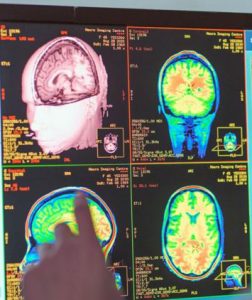

कॅम्ब्रिज विद्यापीठाच्या वैज्ञानिकांनी 0-90 वयोगटातील 3800 लोकांच्या मेंदूच्या एमआरआय स्कॅनचे अध्ययन केले आहे. यातून मानवी मेंदू आयुष्यात केवळ 4 वेळा अचानक अत्यंत मोठा बदल करत असल्याचे कळले आहे. उर्वरित काळात हा मेंदू अचानक बदलत राहतो. 9 वर्षे, 32 वर्षे, 66 वर्षे आणि 83 व्या वर्षी हा बदल होत असतो.